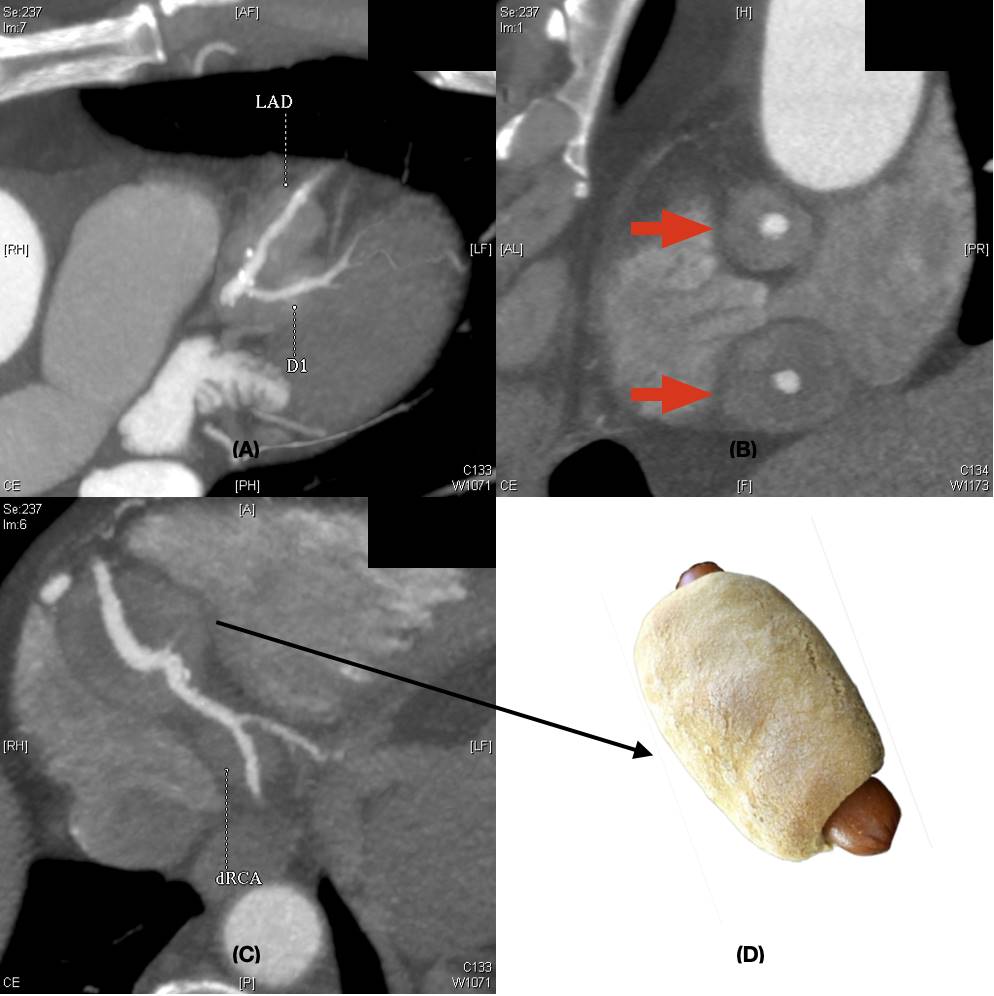

The patient was a 74-year-old Chinese male who presented with left hemiparesis due to intra-cranial haemorrhage in the right thalamus. He had history of hepatitis B carrier status, bronchiectasis and hyperlipidaemia. He was referred for echocardiogram, which showed a large solid-looking “tumour” mass (2.2 × 2.3 cm) in the right atrioventricular groove with mass effect (Figure 1). Magnetic Resonance Imaging scan of the heart showed a concentric mural lesion (measuring 3.2 × 2 × 2.3 cm) encasing the mid-to-distal right coronary artery (RCA) and a similar but smaller concentric mural lesion encasing the mid-left anterior descending artery (LAD). Computed tomography (CT) coronary angiogram showed non-obstructive coronary artery disease with multiple segments of concentric mural thickening around the RCA, LAD, diagonal artery and left circumflex artery (LCx), compatible with coronary arteritis. The largest lesion at mid-distal RCA had the appearance of a “pig-in-a-blanket” (Figure 2). Serum IgG4 level was grossly elevated at 9.85 g/L (normal range 0.04 - 0.86 g/L). The diagnosis of IgG4 coronary arteritis was made. Further assessment of the extent of the disease was performed by PET/CT scan with 18F-fluoro-deoxy-glucose (FDG) and 68Ga-Fibroblast Activation Protein Inhibitor (FAPI) tracers. PET/CT demonstrated mild 18F-FDG and 68Ga-FAPI activity at the soft tissue densities along the LAD, RCA and LCx, suggestive of inflammation along the coronary arteries (Figure 3). A small 68Ga-FAPI-avid focus at pancreatic head, suggestive of same disease involvement, was not detectable by 18F-FDG scan. While the 18F-FDG scan showed mild grade activity along the ascending and descending thoracic aorta and lymph nodes (non-specific findings), activity was not detectable on the 68Ga-FAPI scan. Bone marrow aspirate was normal and did not show any increase in plasma cells. Despite the lack of symptoms, treatment was indicated to prevent the progression of IgG4-RD in the heart and other major organs. In view of his hepatitis B carrier status, it was decided not to give him glucocorticoid therapy. He was given 8 doses of intravenous rituximab (an anti-CD20 antibody) at 375 mg/m2 weekly for 4 doses followed by 375 mg/m2 once every 2 months for 4 more doses with good serological response (Figure 4). He had good recovery from his stroke and remained free from any cardiac symptoms. Repeat CT coronary angiogram after the rituximab therapy showed similar mural thickening around the coronary arteries with no change in the size of the largest pseudo-tumour around the RCA.

Figure 2. (A) CT coronary angiogram showing soft tissue density around the left descending artery (LAD) and first diagonal artery (D1) (B) CT coronary angiogram showing the concentric mural thickening around the proximal and distal right coronary artery, giving the appearance of pseudo-tumours (red arrows). (C) CT finding of large soft tissue density around the mid-right coronary artery looked similar to a “pig-in-a-blanket” (D).